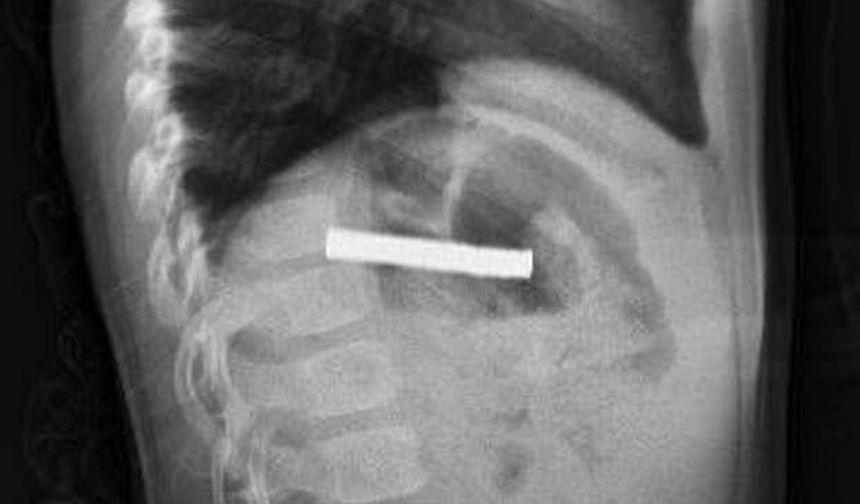

Ağrı'da Genç Kadının Midesinden Endoskopiyle 2 Kalem Çıkarıldı